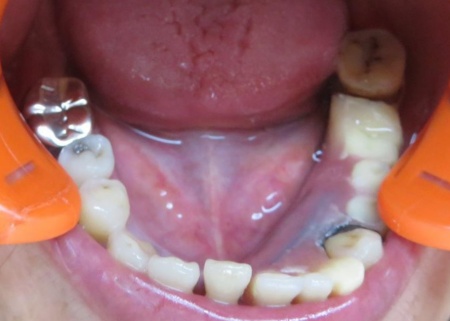

治療中

補強線をいれるための溝を作ります。

補強線を入れました。

治療後